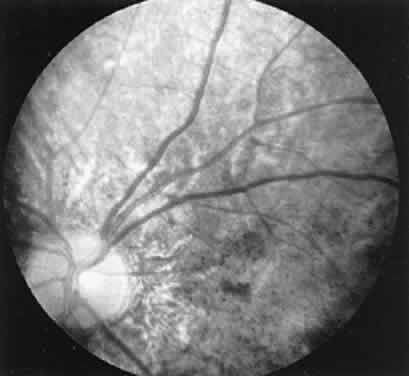

CASE 3 (FIG. 10). A 57-year-old female was referred because of increasing complaints of difficulty with her night vision and her side vision. She had a long history of low-grade uveitis and a progressive decrease in central vision. Visual acuity 20/100 OD, 20/80 OS. The vitreous showed multiple small cells. Both retinas showed narrowed arterioles and strands of pigment in the far periphery. Multiple areas of atrophy of the RPE were seen throughout. An ERG was extinguished.

Fig. 10. Case 3. Left. Posterior pole. Right. Peripheral retina. See text for details.

This patient had birdshot choroiditis, an inflammatory disorder of the choroid with severe secondary photoreceptor degeneration. The ERG gives evidence of widespread degeneration, but the history and clinical findings preclude the diagnosis of a generalized heredoretinal degeneration. This disorder of birdshot choroiditis may produce a “pseudo-retinitis pigmentosa” picture8 (Table 2).